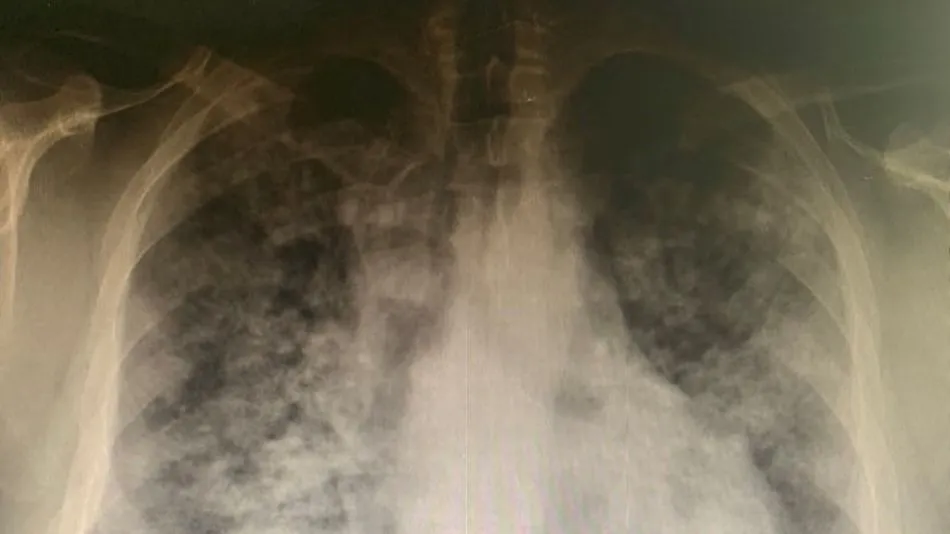

Complejo Asistencial Universitario de Salamanca

30/04/2021 00:00PERMANECEN INGRESADOS 55 PACIENTES

Estabilidad en la cifra de hospitalizados por Covid-19 en Salamanca, con un tímido descenso en UCI

A punto de finalizar abril, este mes se han registrado 12 fallecidos en el hospital, una cifra inferior a la registrada durante todo el mes de marzo (16 fallecidos)